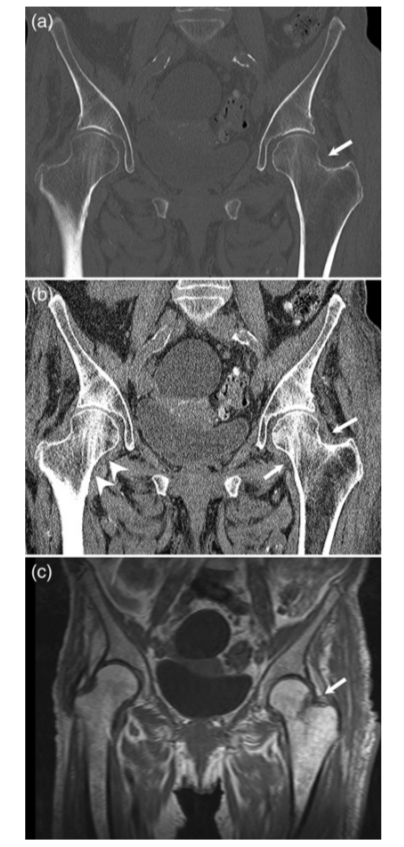

② 髋关节

病例4股骨颈骨折,在CT横断面骨窗上未见明显液体分层(a),在软组织窗(b)可见高密度血肿影(箭头所示,CT值为50HU)。

病例5股骨颈骨折,在CT横断面软组织窗上可见在髂腰肌内出现积脂血症表现。

病例6 一例82岁髋部外伤患者,非移位股骨颈骨折,在CT横断面可见积脂血症,MR证实股骨颈骨折。关节积脂血症在非移位股骨颈骨折的识别中作用明显。